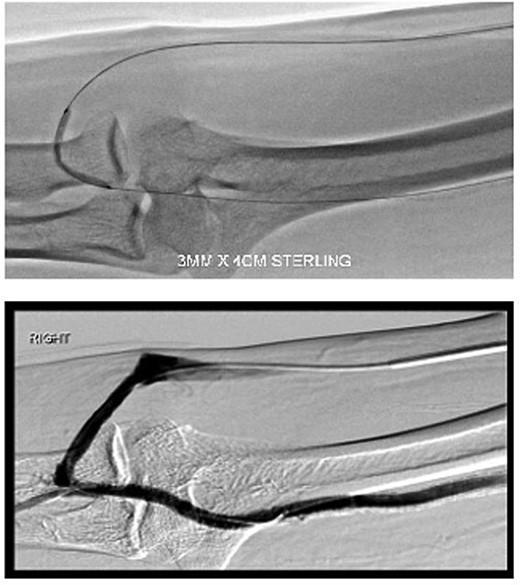

During the procedure, juxta-anastomotic and anastomotic stenoses of up to 75% were treated using non-compliant Mustang™ (Boston Scientific) balloon catheters (5 × 40 mm and 6 × 40 mm), inflated serially at 20 atm for 2 minutes each (Fig. 2). There was an improved palpable thrill after the angioplasty.

Angioplasty of the arteriovenous fistula 2 days prior to clinical presentation.